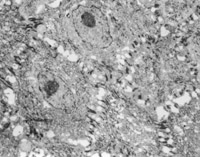

經(jīng)MEBT/MEBO治療5天,可見(jiàn)創(chuàng)面纖維細(xì)胞,成纖維細(xì)胞生長(zhǎng)比較活躍(圖5-3-13)。

5-3-13 MEBT/MEBO治療5天,成纖維細(xì)胞生長(zhǎng)活躍  TEM×2000